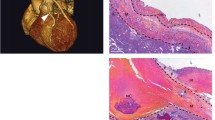

The H and E and pentachrome (Figs. 4 and 5) staining of the grafted vessels revealed complete occlusion and was covered with fibrous tissues. The SEV control tissue displayed intact endothelium with well-organized medial layer whereas the graft was completely occluded with fibrous tissue adhesions as evident by the increased collagen staining. The ECM disorganization was observed in the graft as displayed by the wavy appearance of ECM fibers with a concomitant increase in elastic tissue. The occluded lumen was infiltrated with vascular smooth muscle cells in the subendothelial layer (superficial to the disrupted internal elastic membrane) showing the neointimal formation and proliferative smooth muscle cells migrated from the tunica media through the disrupted internal elastic membrane. In addition, the expression of endothelial biomarker CD31 was evident in the graft tissue and SEV control (Fig. 6). However, the expression of CD31 in the graft was irregular as the layers were not clearly defined due to fibrosis. Importantly, the presence of CD31 signifies the existence of vascular tissue remnants in the occluded graft.

A representative H and E staining of the thin section of the grafted vessel showing complete occlusion. The SEV was used as the conduit for coronary artery bypass graft. Panel (A) represents the SEV control harvested from an atherosclerotic pig fed with HFHC diet, and Panel (B) represents the post-CABG graft harvested after 6 months of surgery. The SEV control displayed intact endothelium (red star) with well-organized medial layer (green star) whereas the graft was completely occluded with fibrous tissue adhesions (black star). This is a representative of 4 Yucatan microswine

A representative pentachrome staining of the thin section of the grafted vessel: the SEV used as coronary artery bypass graft. Control SEV in panel (A) displays intact endothelial layer (Yellow star) and medial layer (Red star) and maintenance of the vessel’s structural integrity. Panel (B) shows severe fibrotic tissue formation as evident by the increased collagen deposition (black star) with a concomitant increase in elastic tissue (blue star). The lumen was mostly occluded with plenty of vascular smooth muscle cells (green star) in the subendothelial layer (superficial to the disrupted internal elastic membrane) suggestive of neointimal formation and proliferative smooth muscle cells which migrated from the tunica media through the disrupted internal elastic membrane. This is a representative of 4 Yucatan microswine

Immunofluorescence analysis for the expression of CD31 in the graft and SEV control. Images in the top row are histological sections of graft and SEV control (second row) Images in the left column show nuclear staining with DAPI; the images in the middle column show expression of CD31 while the images in the right column show overlay of CD31 with DAPI. Images were acquired at 20 × magnification